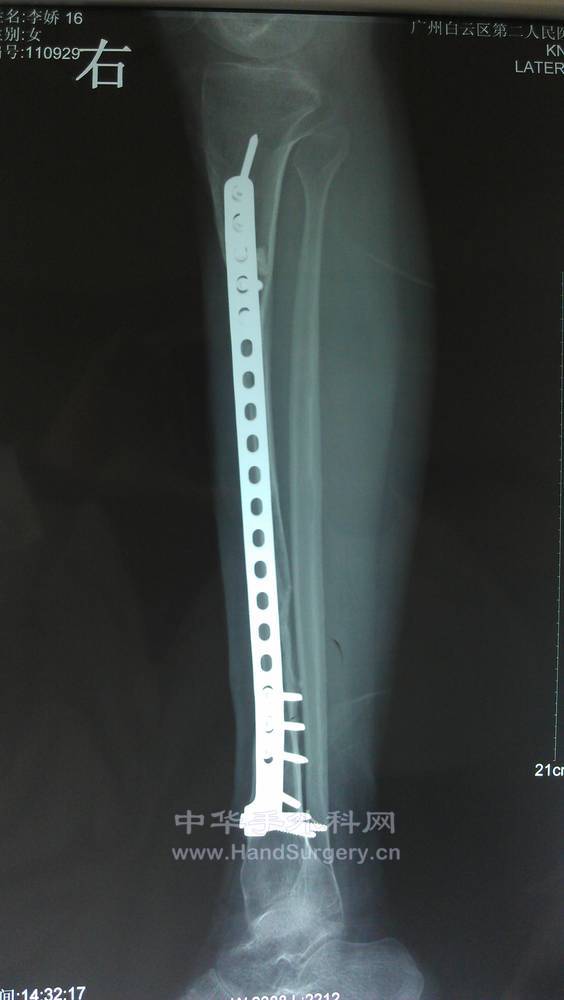

1年后复查的X线片。患者恢复功能很好。

IMAG0177.jpg

IMAG0178.jpg